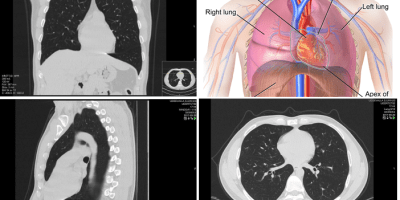

Machine Learning, Medicine, radiology Automatic Interpretation of Chest CT Scans with Machine Learning March 5, 2020